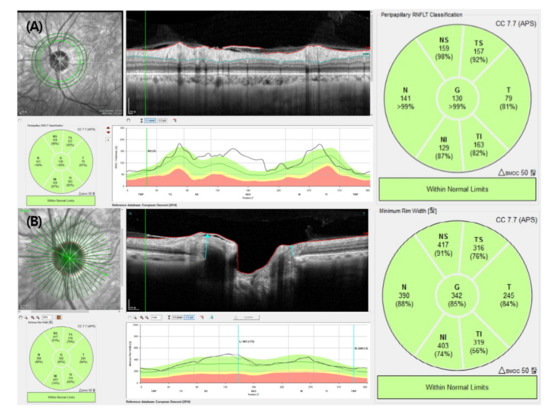

Ejercicio 5.3 El conjunto de datos glaucoma.csv contiene información sobre el grosor de los sectores de los anillos peripapilares de la capa de fibras nerviosas de la retina obtenidos mediante tomografía de coherencia óptica (OTC) en pacientes con y sin glaucoma. En la OTC se toman 4 anillos con distintos radios (BMO, 3.5 mm, 4.1 mm y 4.7 mm) y para cada anillo se miden 6 sectores (Nasal Superior, Nasal, Nasal Inferior, Temporal Inferior, Temporal y Temporal Superior) y también la media global. Los datos están ya normalizados.

Tomografía de coherencia óptica